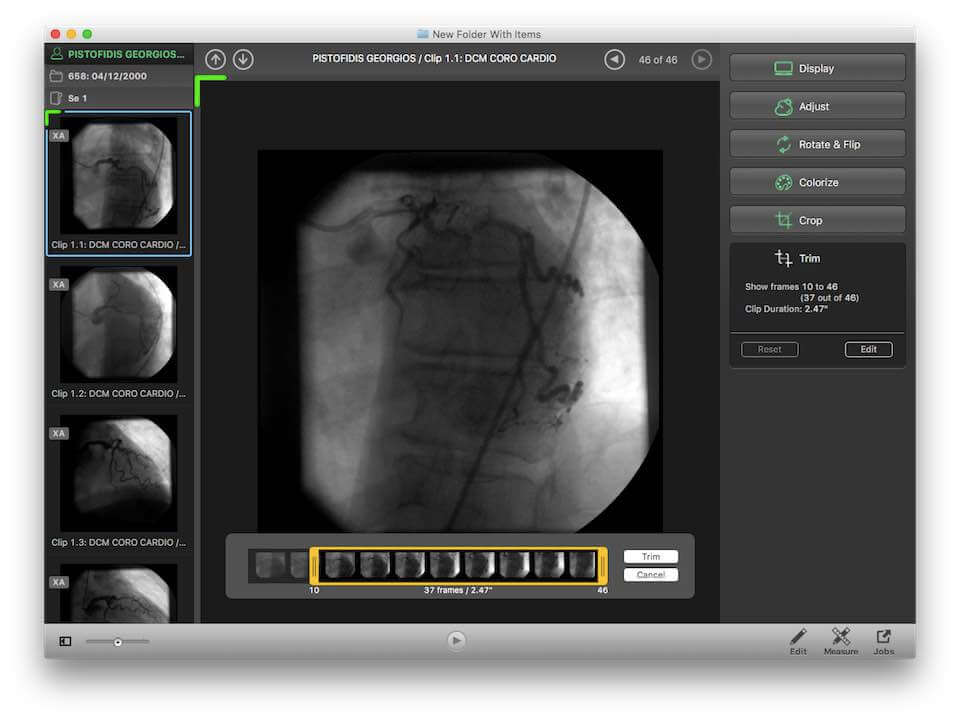

Horos is an open source DICOM viewer for Mac. It is actually the free version of an expensive DICOM viewer called Osirix MD, which is often considered to be the best DICOM viewer for Mac. It only runs on Mac OS, version 10.8 or higher. This software allows for most diagnostic techniques, including multiplanar reconstruction, maximum intensity projections, and volume rendering. It also has tools for manipulating images and making measurements.

One of the unique features of Horos is that it has a plug-in that allows uploading of images to Radiopedia, an online resource with a large number of reference cases and articles. Technical support is available through both phone and email. Horos, however, does not integrate to PACS free of cost. Cloud-based storage is available at an additional cost.

A free version of Osirix MD, called Osirix Lite, is also available to users. However, it does not allowing editing of imaging metadata, and image modifications come with a watermark. While this is good to get a feel for the parent software, it is not intended for regular medical use.

| 2. | Horos | Mac OS | Available for extra fee | Y | Y | Y | N.A. | N.A. | i5 processor/ 16 GB RAM | Open source |